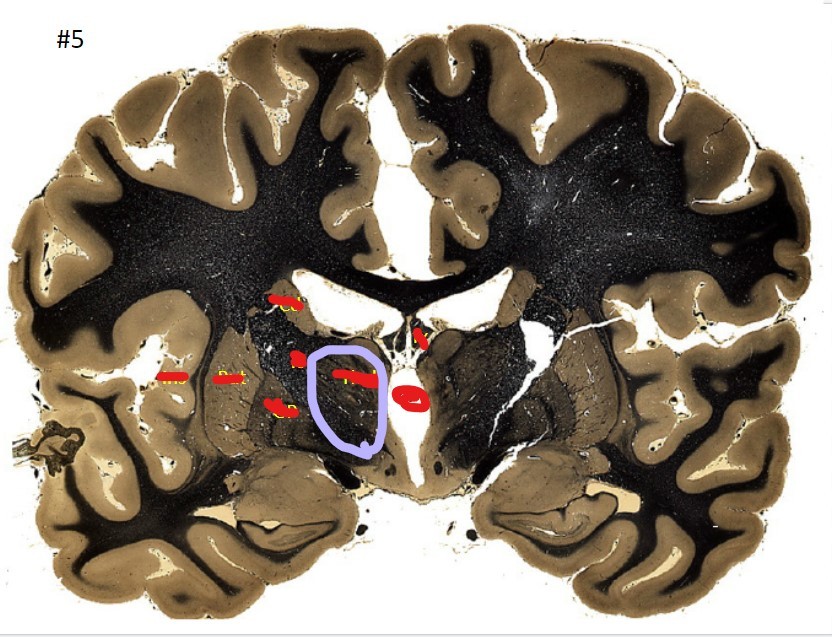

Q

what is the circled area (#5)?

A

the caudate nucleus

20

21

the 3rd ventricle

22

23

the globus pallidus

24

25

the internal capsule

26

the putamen

27

the amygdala

28

the beginning of the hippocampus